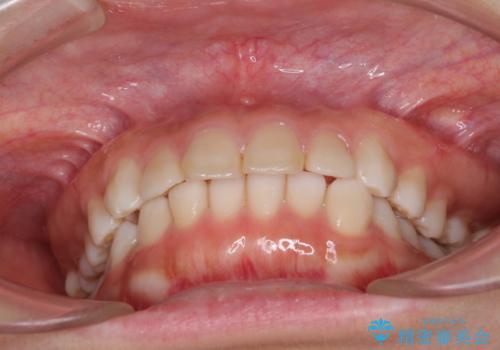

インビザラインによる軽度な出っ歯の矯正治療

- 上の前歯の出っ歯を治したいとのことで来院された患者様です。

上下顎ともにIPR(歯と歯の間を削る)と歯列全体の拡大によって口元が引っ込むように設計し、インビザラインにより治療を行うこととしました。

どこまで口元を引っ込めることができるのか、患者様自身も正直分からない部分があったため、少しずつ治療ゴールを変更しながら仕上げていきました。

気になっていた前歯の飛び出した印象は、最終的にはスッキリと引っ込み、大変満足していただきました。